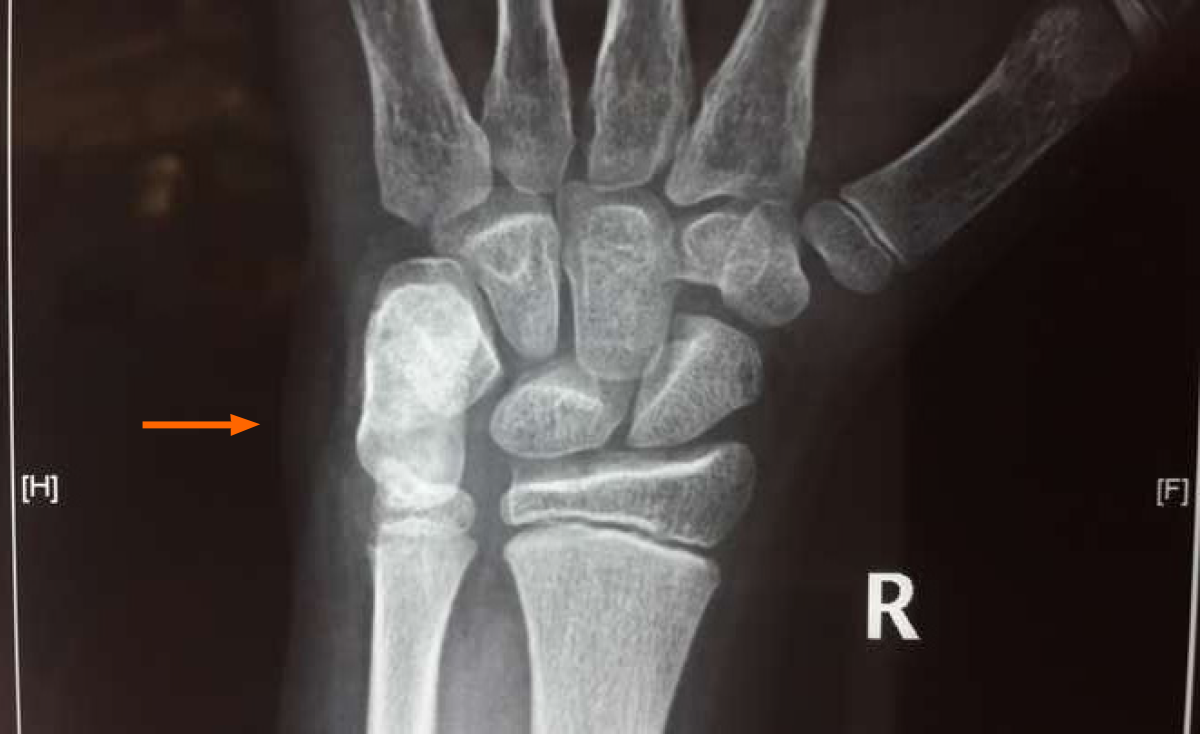

Figure 1

Radiographs suggestive of an elongated ossified mass arising from the volar aspect of the pisiform bone (orange arrow marked).